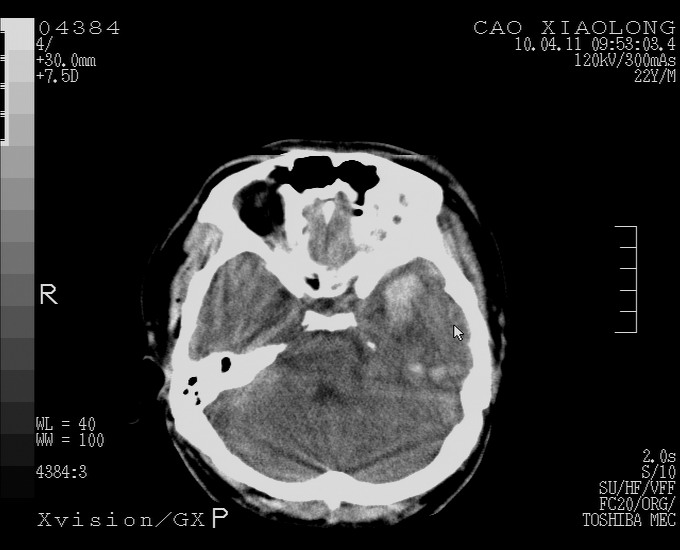

以下是引用随光逐影在2010-4-11 11:00:00的发言:[br]1)左侧额颞顶部硬膜下血肿。2)蛛网膜下腔出血。3)右侧颞顶部颅骨线形骨折。[br][br]20小时后复查:左侧额颞叶脑挫裂伤;左侧额颞顶部硬膜下血肿及蛛网膜下腔出血有吸收表现;右侧颞顶部颅骨线形骨折。[br]